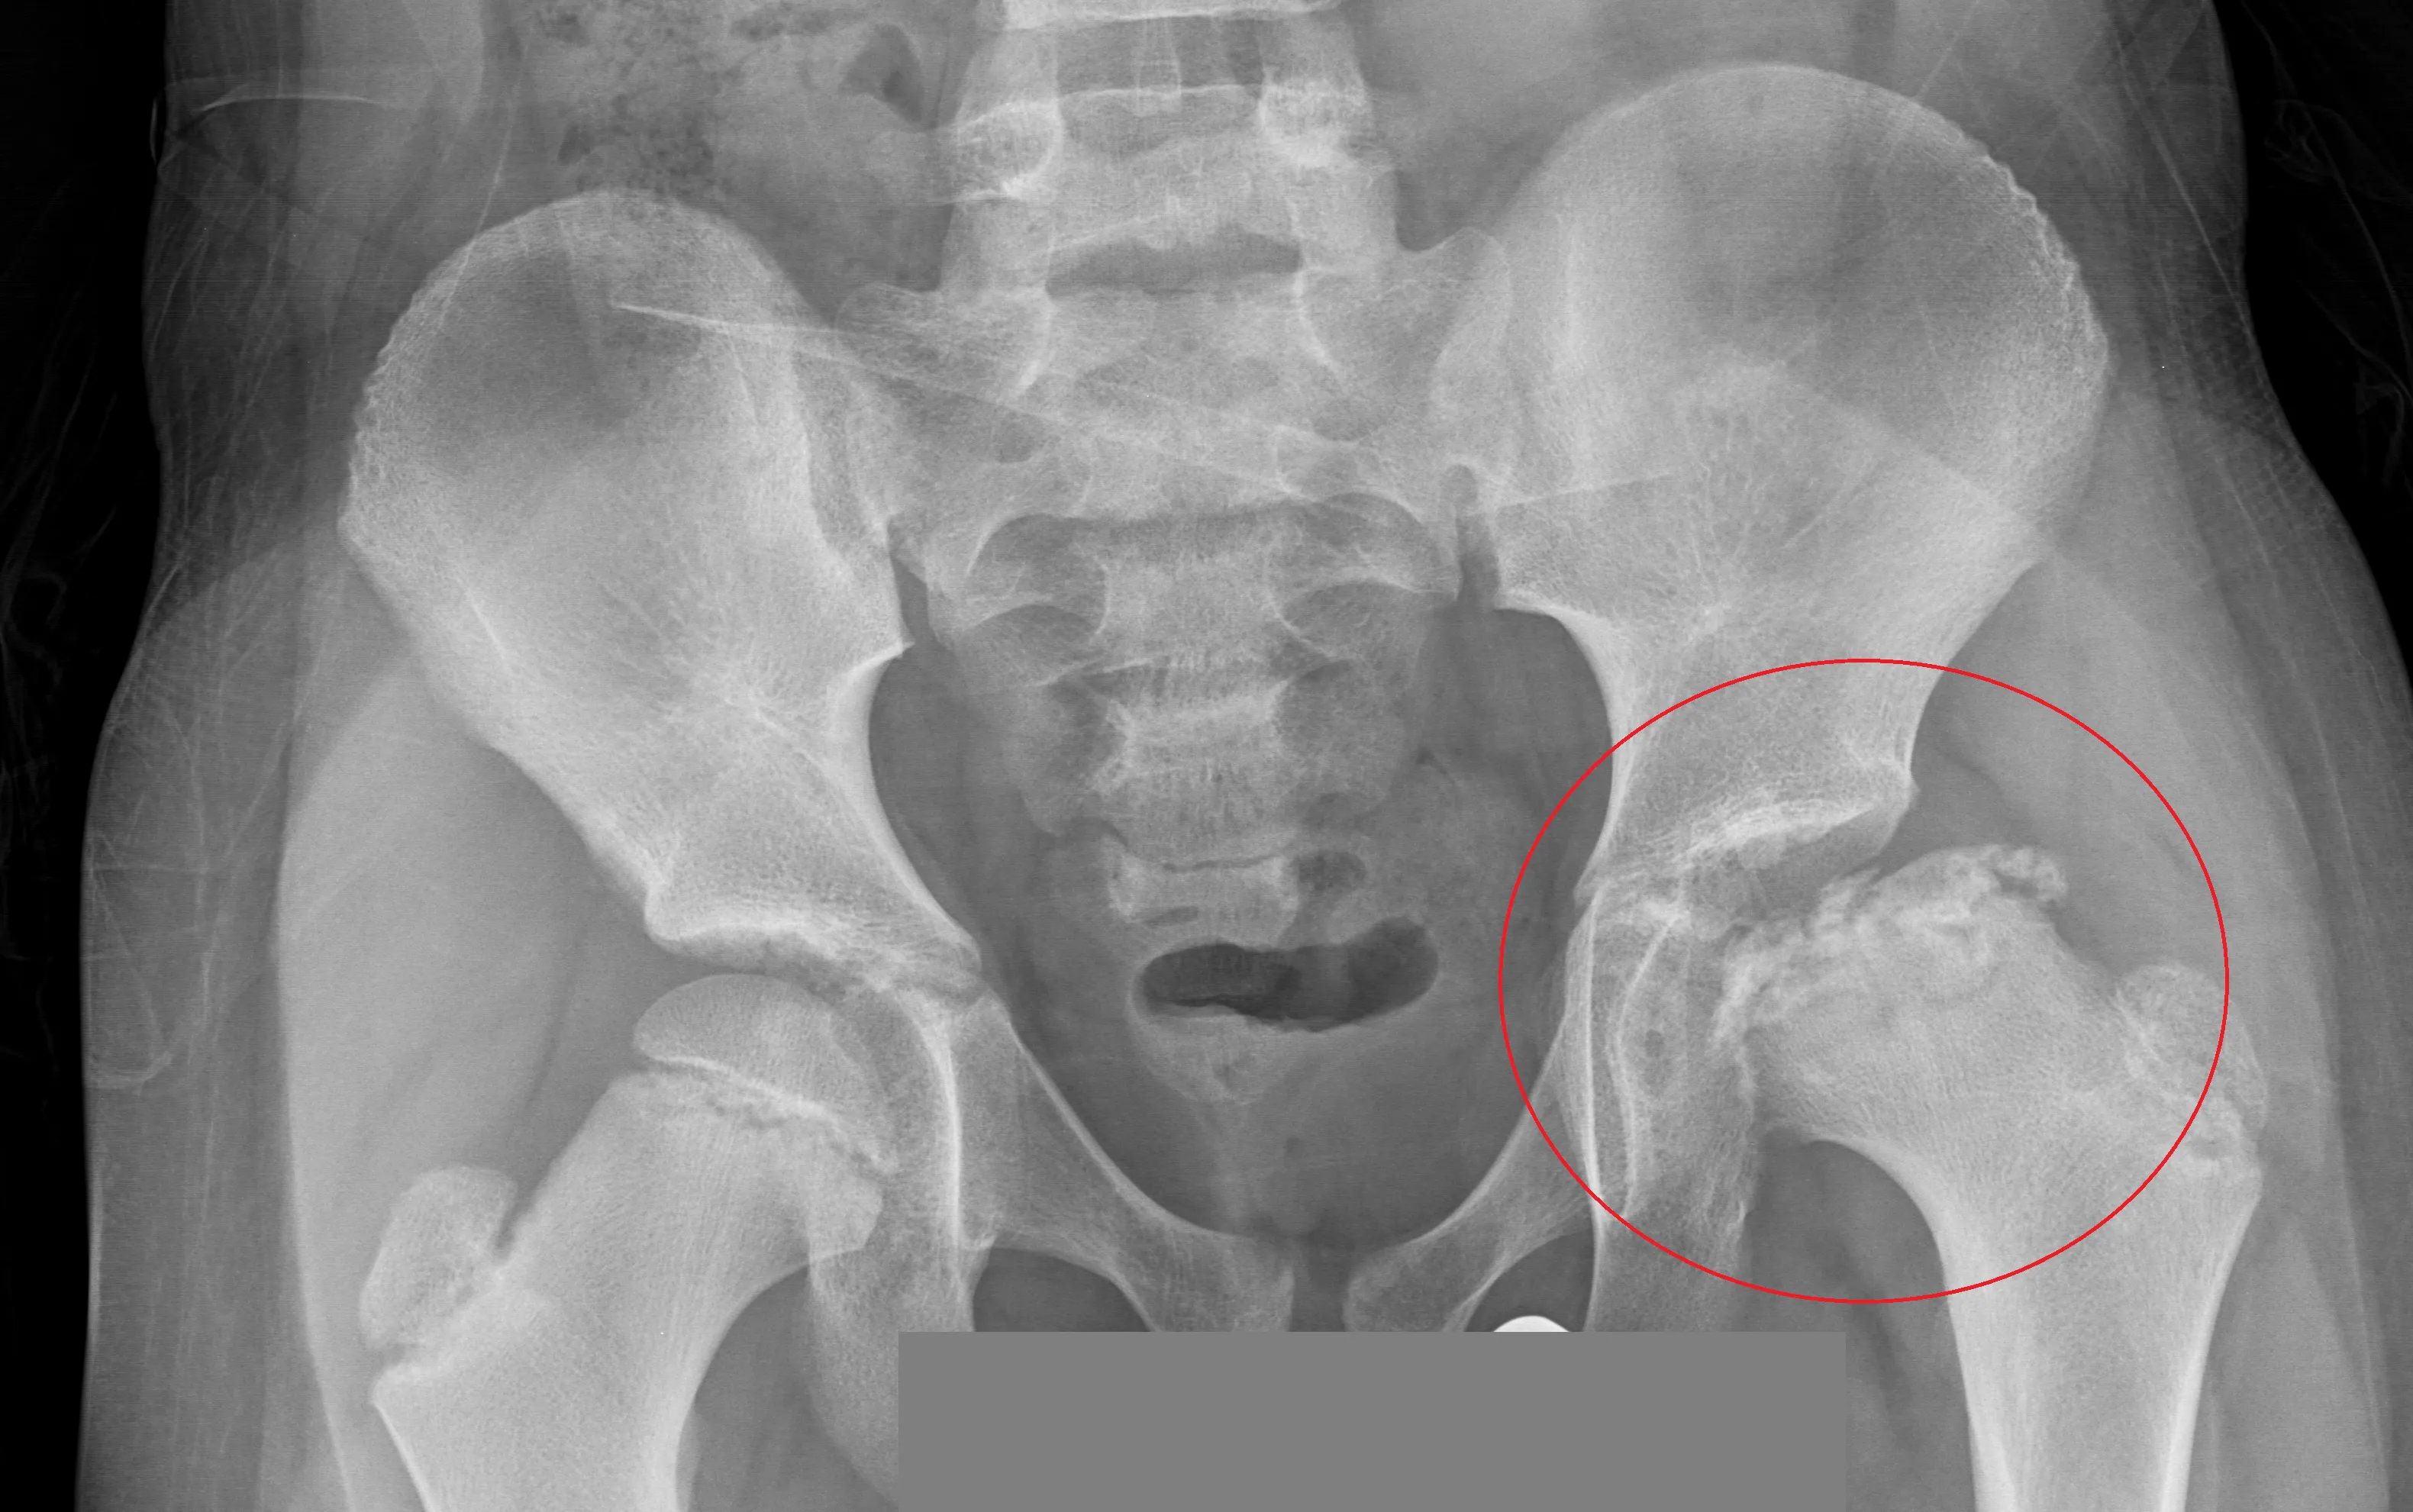

Criança de 6 anos com claudicação e essa radiografia.

Doença de Legg-Calvé-Perthes (DLCP)

RX de quadril em AP e Lauenstein (posição de rã).

Revela colapso da epífise femoral e aumento do espaço articular.

RX de quadril em AP e Lauenstein (posição de rã).<br>Revela colapso da epífise femoral e aumento do espaço articular.